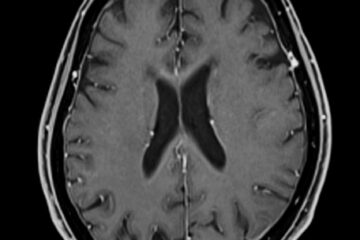

Pirmiausia gydytojas apžiūri ranką, įvertina, kada atsirado gumbas ir ar yra kitų nusiskundimų. Dažniausiai atliekama rentgeno nuotrauka, padedanti atskirti išaugą nuo kitų riešo pažeidimų. Jei reikia, galima atlikti papildomus tyrimus – ultragarsą, magnetinio rezonanso tomografiją, kartais elektromiografiją ar kompiuterinę tomografiją.